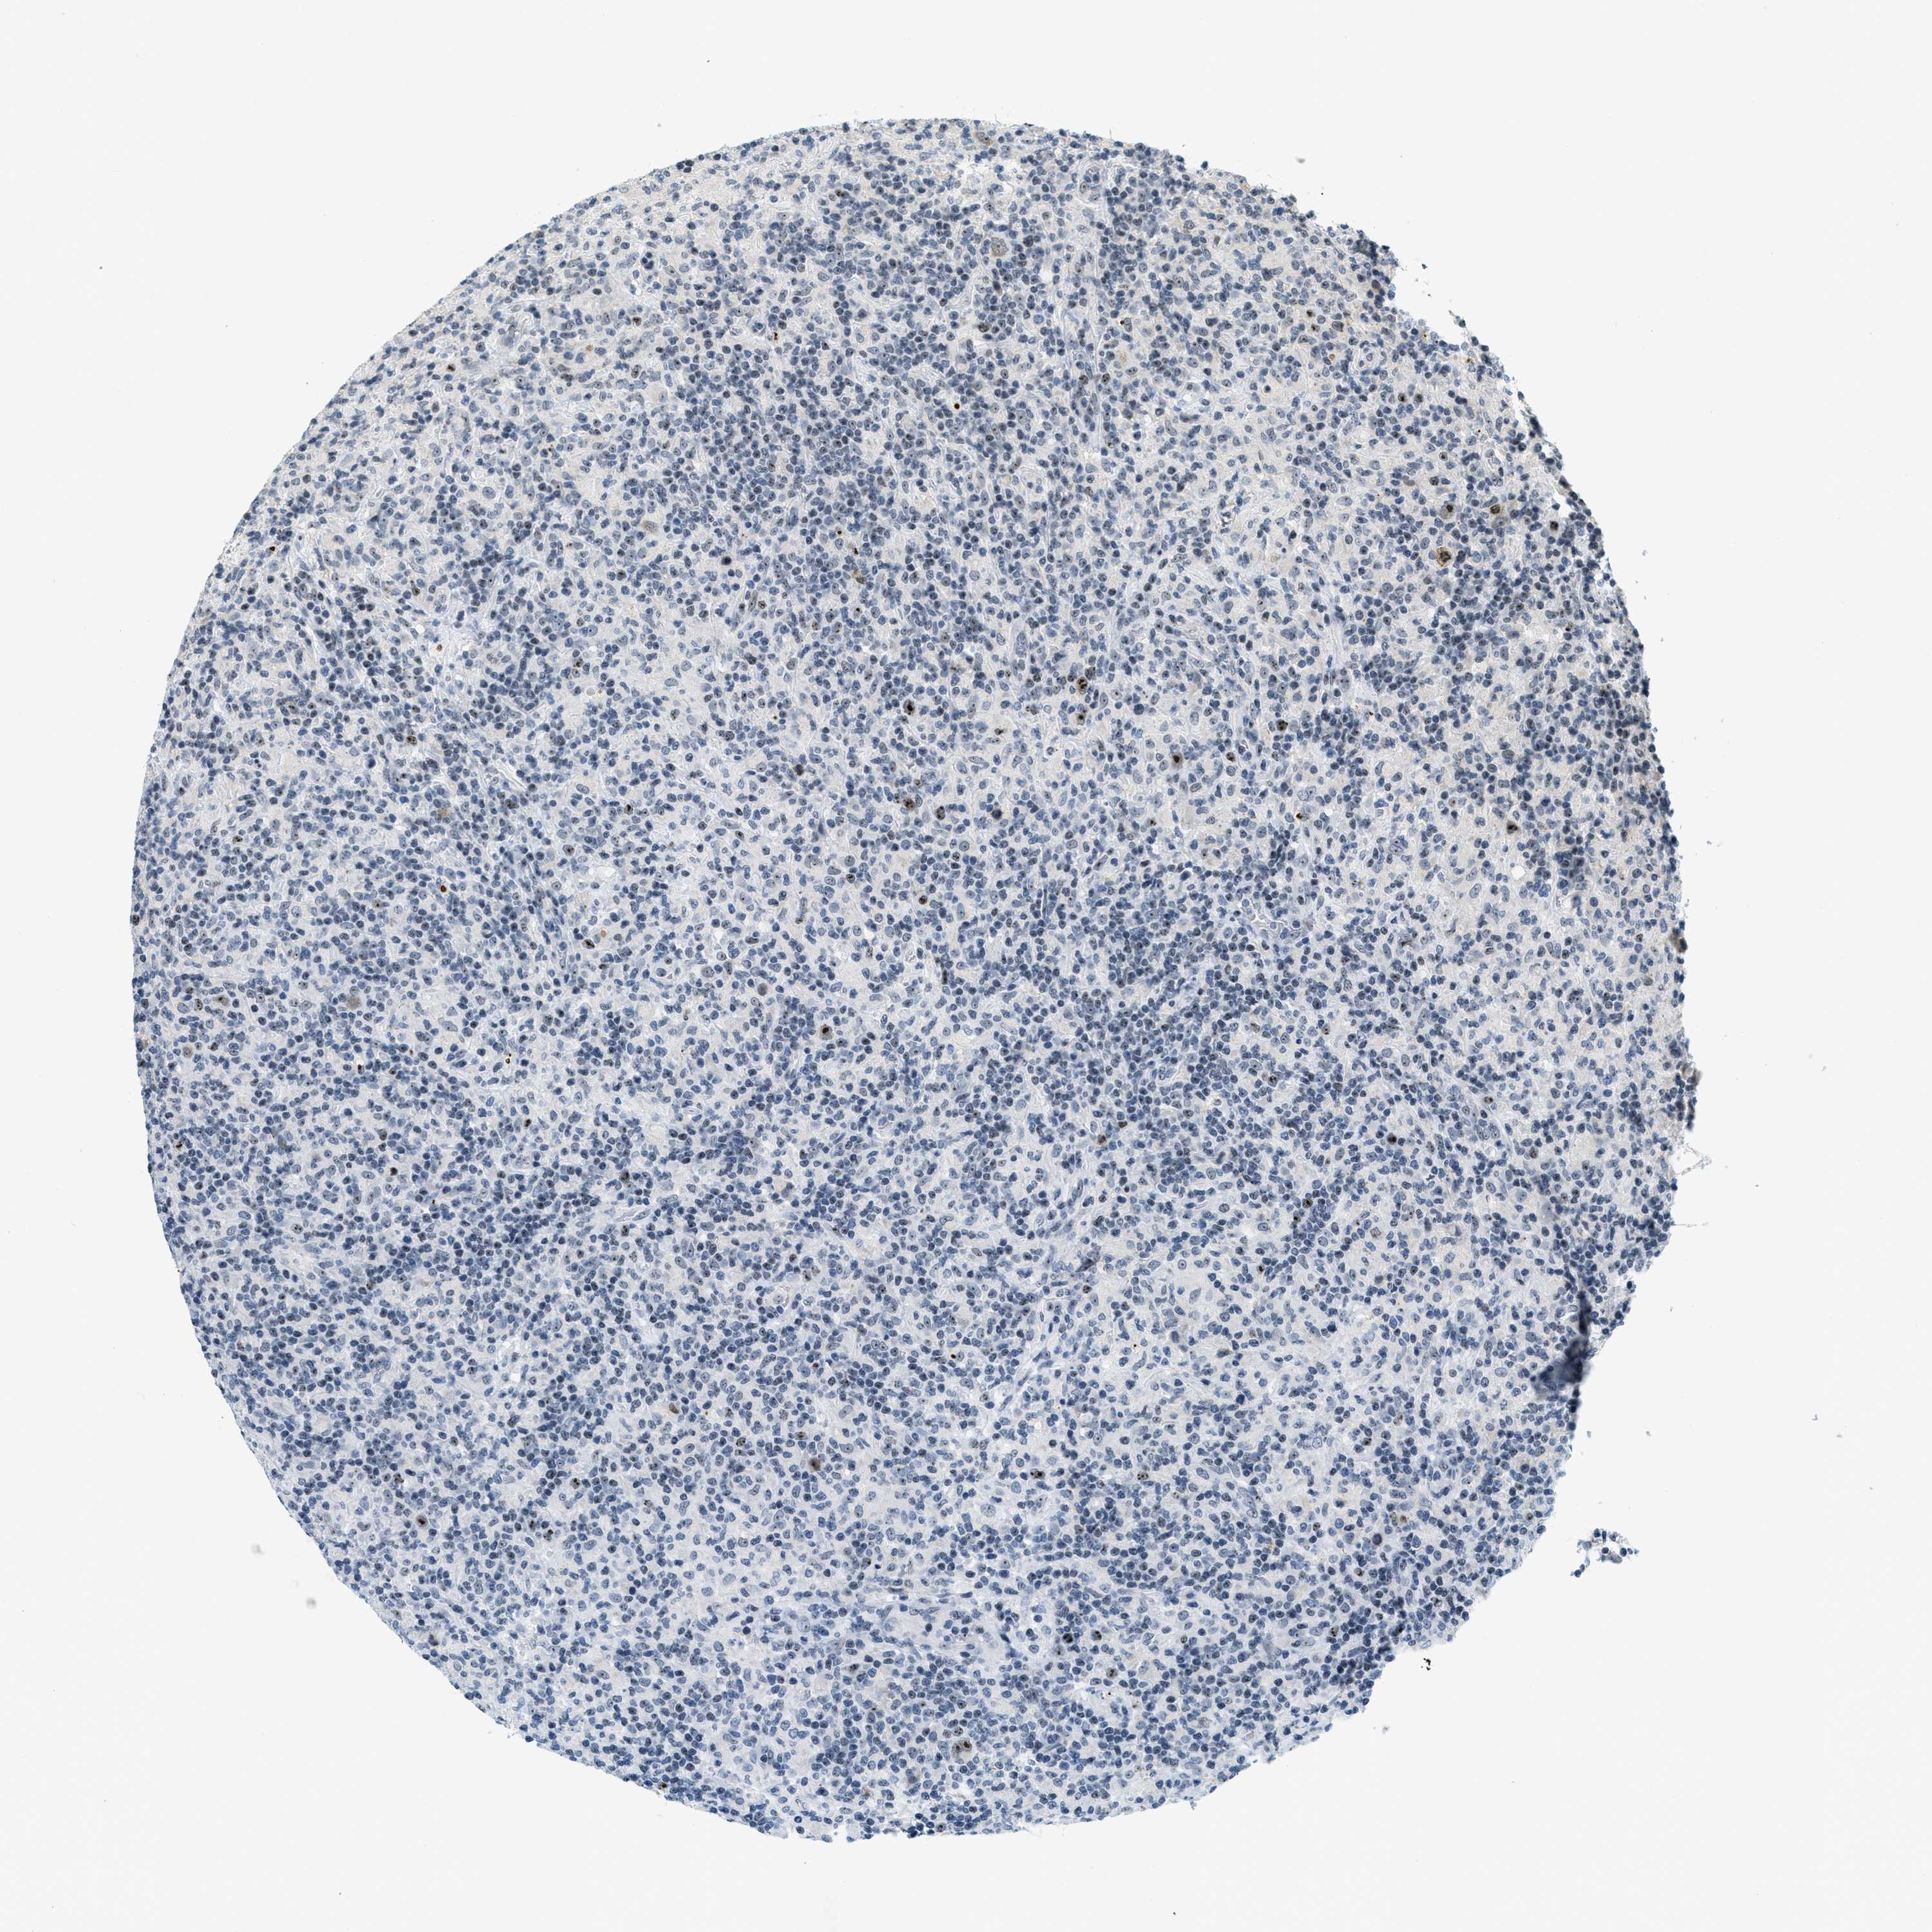

LYMPHOMA - Protein expressioni

A mouse-over function shows sample information and annotation data. Click on an image to view it in a full screen mode. Samples can be filtered based on level of antibody staining by selecting one or several of the following categories: high, medium, low and not detected. The assay and annotation is described here.

Antibody stainingi

Antibody staining in the annotated cell types in the current human tissue is reported as not detected, low, medium, or high, based on conventional immunohistochemistry profiling in selected tissues. This score is based on the combination of the staining intensity and fraction of stained cells.

Each image is clickable and will lead to virtual microscopy that enables deeper exploration of all samples and also displays staining intensity scores, fraction scores and subcellular localization as well as patient and tissue information for each sample.

Antibody HPA014855

Hodgkin's disease, NOS

Malignant lymphoma, non-Hodgkin's type, High grade

Malignant lymphoma, non-Hodgkin's type, Low grade